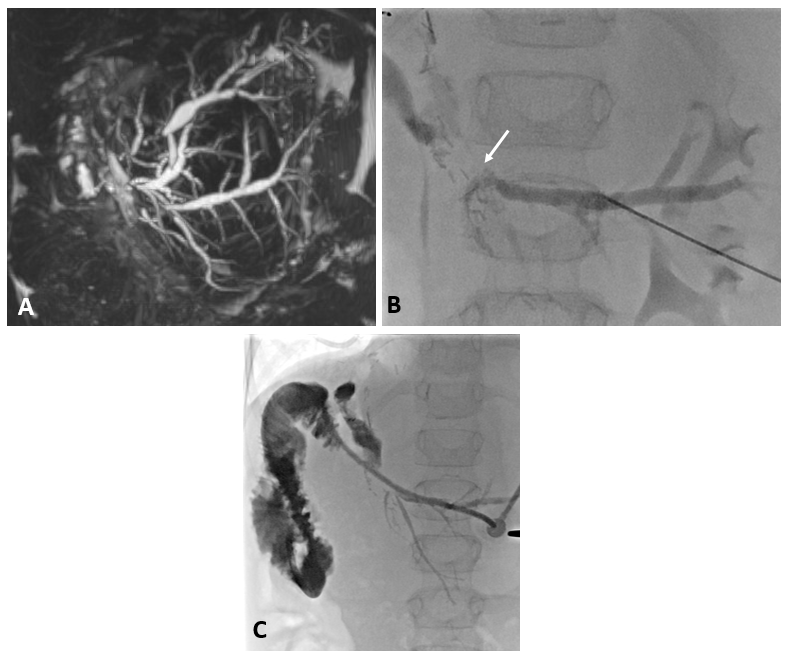

8 jähriger Junge nach Transplantation der linksseitigen Lebersegmente

In der Bildgebung (MRCP-Bild, A) zeigt sich eine Erweiterung der Gallenwege in der Leber, bedingt durch eine Engstelle an der Verbindung der Gallenwege (Gallenwegsanastomose). Entlastung der gestauten Gallenwege mittels PTCD. Punktion eines in der Leber gelegenen Gallenweges mit Hilfe von Ultraschall. Gabe von Kontrastmittel über die Punktionsnadel (B). Darstellung des gestauten Gangsystems und der Engstelle (Pfeil). Anschließende Anlage einer Ableitung (Drainage) zur Entlastung des Gallenwegssystems (C).

Abb 1

A

3- jähriger Junge mit stattgehabter Pfortaderthrombose (Verschluss der Pfortader).

Zustand nach Anlage eines Meso-Rex Shunts. Aktuell Größenzunahme der Milz und zunehmende Zeichen des Pfortaderhochdrucks. Sonographisch wurde dann der Verdacht auf eine Stenose (Verengung) der Shunts gestellt. In der Angiographie mit einem Zugang über Milz zeigte sich die vermutete Stenose (Pfeil in Bild A). Es wurde dann ein Stent eingebracht und mittels Ballon dilatiert (B). In der Kontrolle zeigte sich ein gutes Ergebnis mit Beseitigung der Engstelle. Dem Patienten ging es rasch besser.